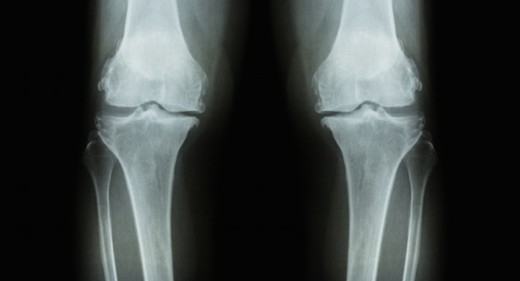

Read More ›A new clinical care standard for the treatment for knee OA has been released by the Australian Commission on Safety and Quality in Health Care earlier this year. The standard states surgery should be a last resort for knee OA and exercise, weight loss and the use of pain relieving medication should be the gold […]